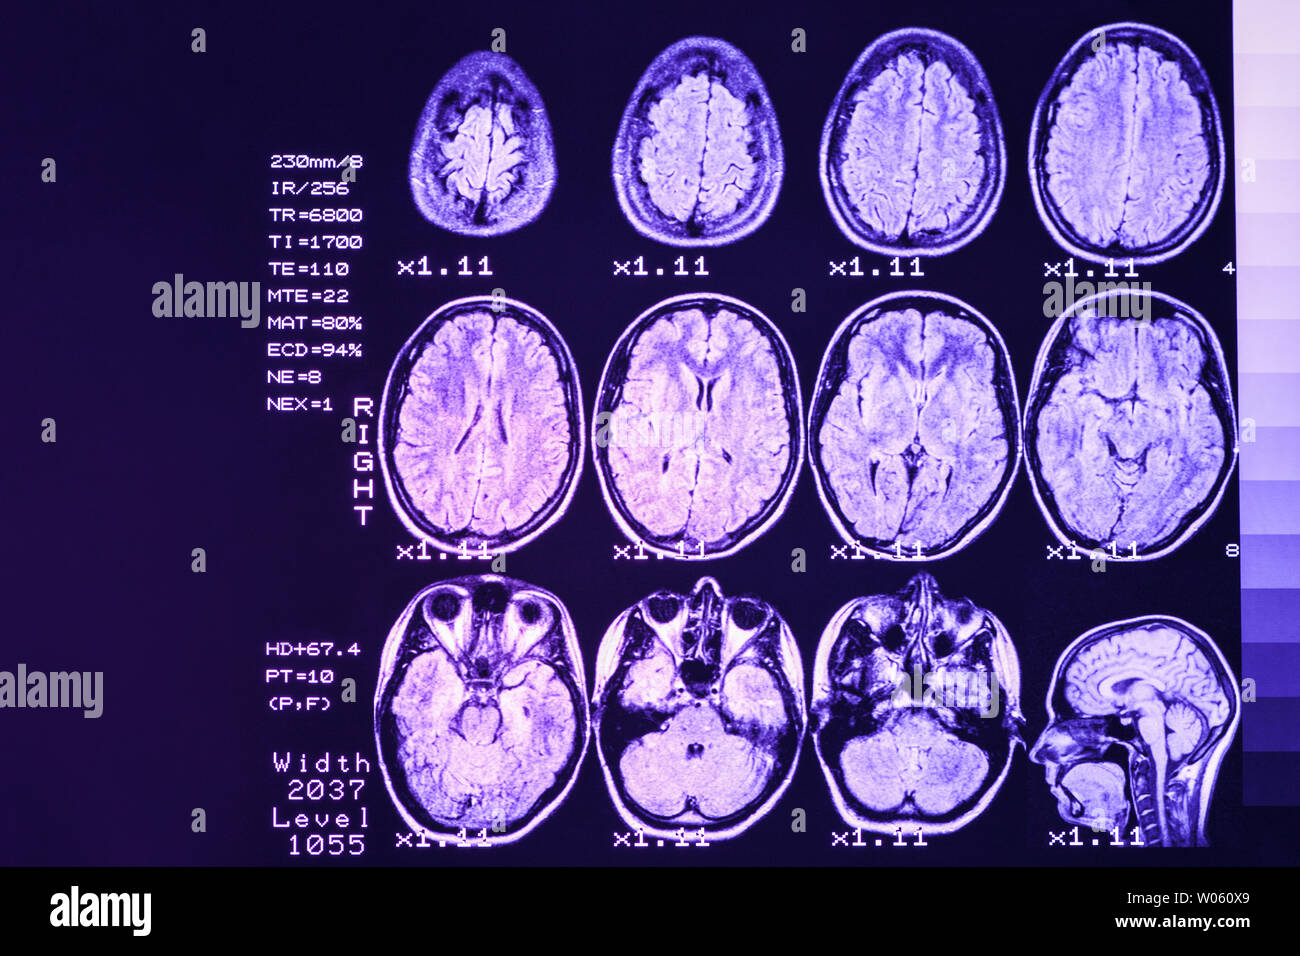

MRI scan or magnetic resonance image of head and brain scan. The result is an MRI of the brain with values and numbers with lilac backlight. Stock Photohttps://www.alamy.com/image-license-details/?v=1https://www.alamy.com/mri-scan-or-magnetic-resonance-image-of-head-and-brain-scan-the-result-is-an-mri-of-the-brain-with-values-and-numbers-with-lilac-backlight-image258287969.html

MRI scan or magnetic resonance image of head and brain scan. The result is an MRI of the brain with values and numbers with lilac backlight. Stock Photohttps://www.alamy.com/image-license-details/?v=1https://www.alamy.com/mri-scan-or-magnetic-resonance-image-of-head-and-brain-scan-the-result-is-an-mri-of-the-brain-with-values-and-numbers-with-lilac-backlight-image258287969.htmlRFW060X9–MRI scan or magnetic resonance image of head and brain scan. The result is an MRI of the brain with values and numbers with lilac backlight.